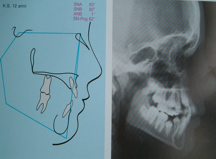

Alterazioni scheletriche antero-posteriori e verticali sono evidenziabili attraverso misurazioni effettuate sulla radiografia del cranio a bocca chiusa nella proiezione laterale : teleradiografia

Sulla quale si tracciano dei punti anatomici, da qui delle misure lineari e angolari che consentono di ricavare valutazioni sulla posizione delle strutture ossee.

-Scheletriche ovvero legate ai rapporti tra mascellari secondo misurazioni effettuate sulla radiografia laterale del cranio (teleradiografia ).